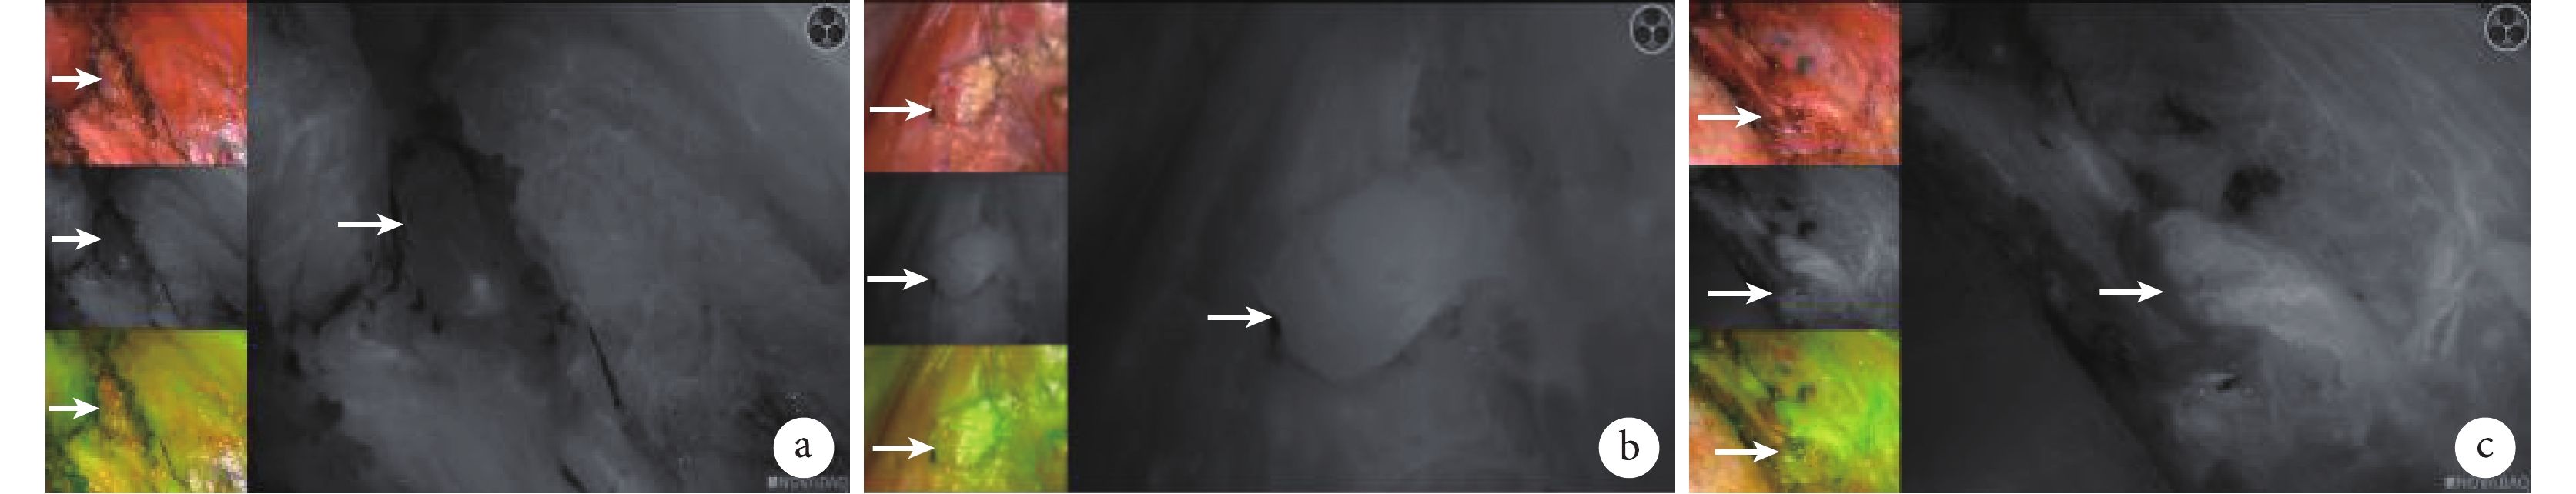

在本研究手術過程中,若發現甲狀旁腺血供可疑損傷(顏色發生改變)時,應根據不同的分組立即采取不同的處理方式,以避免長時間的缺血導致甲狀旁腺壞死,具體處理如下:① 研究組:將 25 mg 注射用 ICG 粉劑溶入 10 mL 無菌水中,立即靜脈注射 3~5 mL ICG 溶液后關閉手術室所有燈光,注射后 1~2 min 內使用 NOVADAQ 熒光成像設備(PC9000)對手術區域進行觀察并采集圖像,對圖像中的甲狀旁腺進行評分[5]:黑色為 0 分,提示甲狀旁腺血供障礙(圖 1a);灰色為 1 分,提示甲狀旁腺血供輕度受損(圖 1b);白色為 2 分,提示甲狀旁腺血供良好(圖 1c)。根據評分結果,對甲狀旁腺采取不同的處理措施[2]:評分為 0 分時采取自體移植;評分為 2 分時采取原位保留;評分為 1 分時,則在手術結束前再次靜脈注射 3~5 mL ICG 溶液后同前一樣操作再次采集圖像評估,若此時評分為 0 分者則采取自體移植,若評分為 2 分者則采取原位保留,若評分仍為 1 分者則再次仔細觀察甲狀旁腺顏色,若顏色無明顯變化則原位保留,若變為深褐色或黑色時則使用針頭挑開甲狀旁腺被膜觀察,若顏色逐漸變淺則原位保留,若顏色不變則自體移植。② 對照組:由主刀醫生肉眼觀察并判斷,若甲狀旁腺顏色變為深褐色或黑色時使用針頭挑開甲狀旁腺被膜觀察,若顏色逐漸變淺則原位保留,若顏色不變則自體移植。

a:呈黑色,評分 0 分,提示血供障礙(白箭所示為甲狀旁腺);b:呈灰色,評分 1 分,提示甲狀旁腺輕度血供損傷(白箭所示為甲狀旁腺);c:呈白色,評分 2 分,提示血供良好(白箭所示為甲狀旁腺)